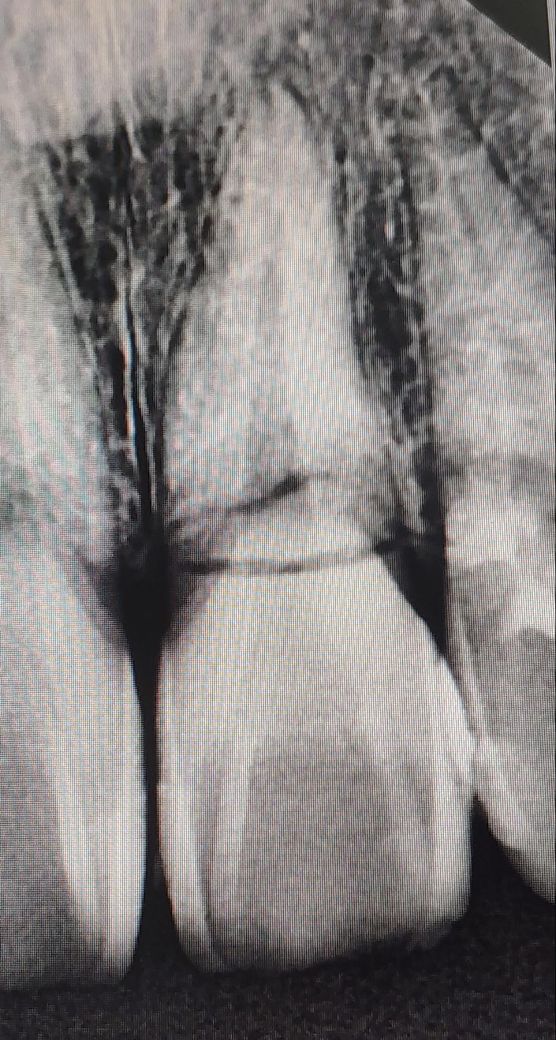

그런데 현재까지 너무 오래 아픈것 같아서 집 근처 치과를 가서 사진을 찍어보니 왼쪽 앞니가 속에서 부러졌다고 합니다.

• 1번 째 사진

현재 사진에서도 파절선이 뚜렷하여 별다른 방법이 없을 것으로 보입니다.